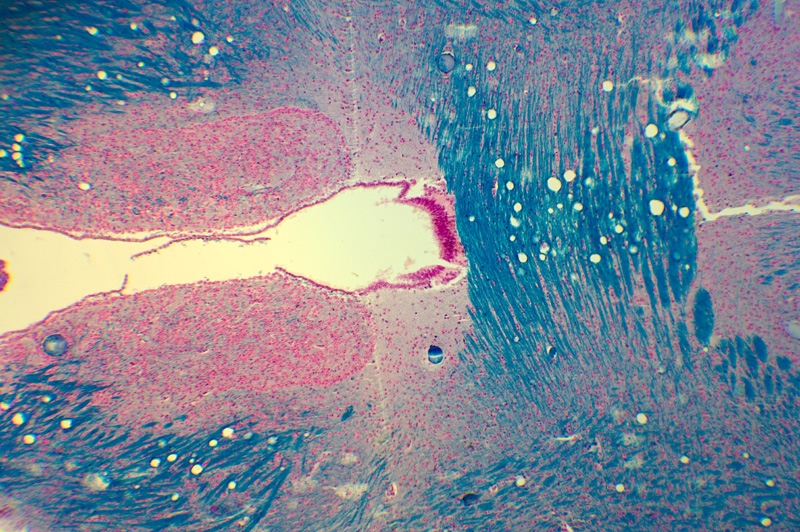

Hallo Ronald, auf dem ersten Bild sieht man ein Foto, dass mit dem Samsung S7 durch ein Periplan GF 10x aufgenommen wurde. Von einem digitalen Zoom habe ich abgesehen. Schade, dass Smartphones keinen 2x optischen Zoom haben. Damit wäre viel gewonnen.

Das zweite Foto enstand mit einer Pentax K-3 über einem Zeiss Kpl W 10x Okular am LEitz Ortholux II. Die Kombination ergibt nur in der Mitte ein gutes Foto; zum Rand hin bricht es ein. Aber es zeigt mehr vom Bild als mein Periplan GF 12,5x MF Okular vor der Kamera, welches das Bild stärker beschneidet.

Ich hätte nichts dagegen, mit der DSLR den vollen oder leicht angeschnittenen Kreis aufzunehmen, weil die Auflösung der Sensoren groß genug für die nachträgliche Auswahl eines Ausschnittes ist.

Tom

Foto mit dem Smartphone Samsung S7

Foto der DSLR und dem Zeiss Kpl W 10x. Das Okular passt nicht zu den Leitz Objektiven, Das sieht man vor allem in Richtung Bildecken an den starken Farbsäumen. Mit meinem Leitz PEriplan GF 12,5 MF ist das Bild besser, aber der Ausschnitt noch kleiner.

Vergleich beider Bilder. Die DSLR nimmt einen zu kleinen Bereich auf.